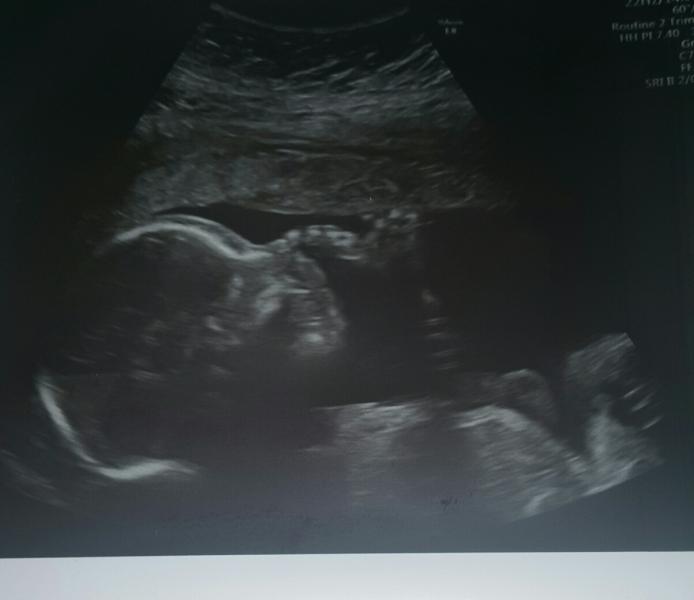

Были сегодня на Узи на Пастера 9, для меня новая локация)) Узист Деришева Ирина Васильевна. Очень понравилась, приятная женщина, сначала сама долго смотрела, а потом как повернула монитор ко мне, и опять эта сказка😇, показала во всех ракурсах малыша, сделала 2 фото, показала в 3д, долго выбирала хороший ракурс, потом сказала фоткай))) сидела со мной 50 минут, заплатила 300 грн. Пришла по записи и попала на свое время. Аппарат у них новый, очень крутой. Если кому нужно, дам номер) 💐💐💐

@victory.sen главное чтоб попой не повернулся))) они такое любят делать))Узист тогда просит вас погулять и скушать шоколадку)

@victory.sen я сегодня как для первой встречи осталась очень довольна) она внимательная) долго показывала малыша) тоже сказала что мальчишка с большим достоинством😂

@_ylia_s08 @_ylia_s08 да, но 3д она не распечатала, можно было только сфоткать на телефон